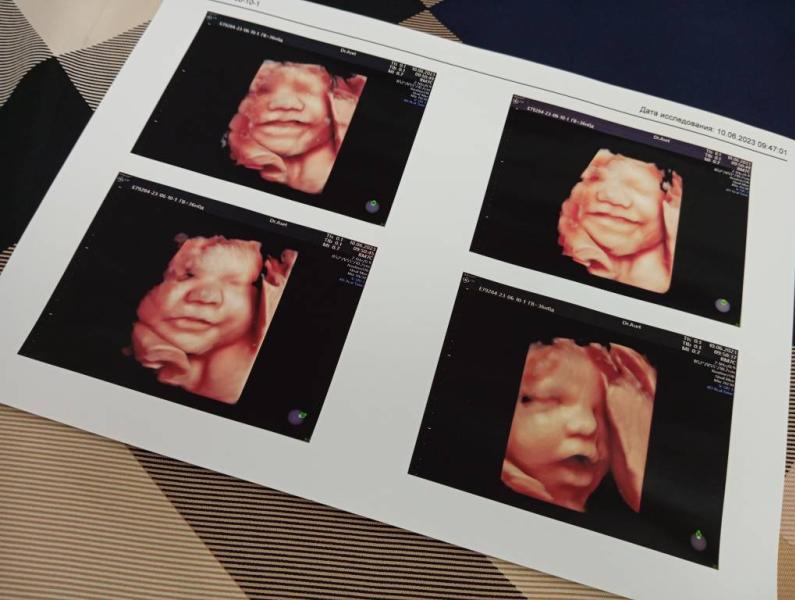

🔥🔥🔥 Жаль , что не все так умеют позировать 😇

Аллох1умма Барик, это на каком неделе сделано скрининг?

Здесь 34 недели уже